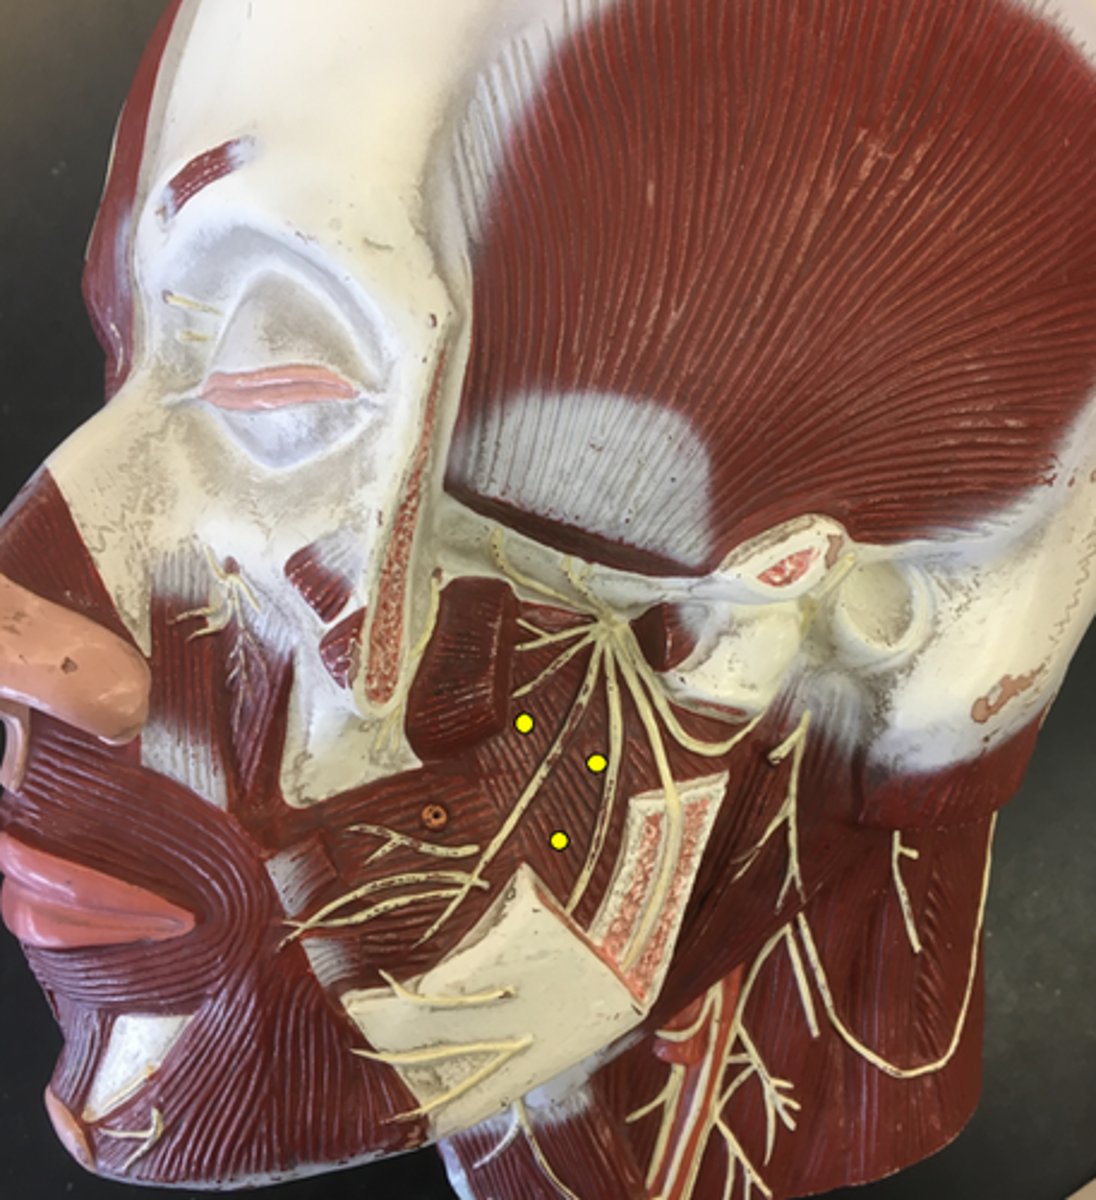

Zygomaticus Major

Zygomaticus Minor

Orbicularis Oris

Levator Labii Superioris

Depressor Anguli Oris

Depressor Labii Inferioris

Mentalis

Buccinator

Temporalis

Masseter